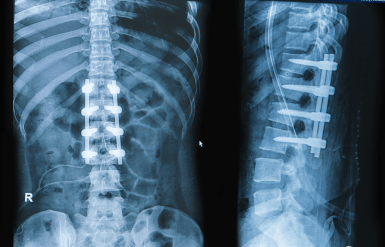

People with intense neck or back pain that come to my clinic often ask, “Do you think I’ll need surgery?” This is a loaded question